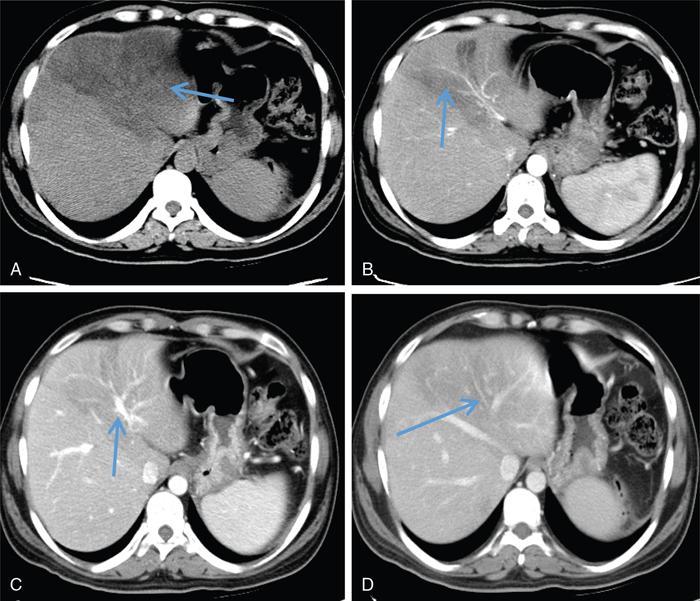

Excessive triglyceride accumulation within hepatocytes is defined as hepatic steatosis. Major conditions associated with hepatic steatosis include alcoholic fatty liver disease (AFLD) and nonalcoholic fatty liver disease (NAFLD). Causes of hepatic steatosis are discussed in Table 9.10.3. NAFLD is the most common form of hepatic steatosis and discussed in detail below. Up to 90% of patients with chronic alcoholic intake have fatty liver. Those with pure AFLD have a 10% risk of progressing to cirrhosis. Consumption of 30 g ethanol/day shows increased risk of chronic liver disease and cirrhosis. Other risk factors include female sex, obesity, cigarette smoking, obesity and associated risk factors. These factors are divided into 2 main categories which can cause fatty liver: inborn errors of metabolism and acquired metabolic disorders. Inborn errors of metabolism include abetalipoproteinemia, galactosemia, glycogen storage disease, hereditary fructose intolerance, homocystinuria and Wilson disease. Inflammatory bowel disease, jejunoileal bypass, malnutrition, starvation and total parenteral nutrition are acquired metabolic factors associated with increased risk. Chronic HCV infection, is associated with hepatic steatosis, with prevalence of 40%–80%. Hepatic steatosis can be seen as an adverse reaction to some medications such as tetracycline, valproic acid, some of chemotherapeutic agents, dexamethasone, amiodarone, methotrexate, tamoxifen and acetylsalicylic acid. Either microvesicular or macrovesicular steatosis can be observed in drug-induced hepatic steatosis. It generally occurs with therapy lasting several weeks or months and is reversible after discontinuation. The leading cause of hepatic steatosis in paediatric population is NAFLD. Six per cent of these patients develop cirrhosis and end-stage disease. Other less common causes include starvation and malnutrition, drugs (glucocorticoids, oestrogens, tetracyclines, and methotrexate), intoxications (carbon tetrachloride, organic phosphates, organic solvents, and alcohol), metabolic disorders, hepatitis C infection, and total parenteral nutrition. NAFLD is defined as steatosis affecting >5% of hepatocytes in the absence of a secondary cause. NAFLD represents a spectrum of disease, ranging from simple steatosis to steatohepatitis through to fibrosis and cirrhosis and in some cases hepatocellular carcinoma. NAFLD is a growing epidemic worldwide in part due to obesity and insulin resistance leading to liver accumulation of triglycerides and free fatty acids. Nonalcoholic steatohepatitis (NASH) is defined by histologic terms as a necroinflammatory process whereby the liver cells become injured in a background of steatosis. 20% of patients with NAFL progress to NASH, which progresses to fibrosis and cirrhosis over a 15-year time period (Fig. 9.10.3). The definition of NAFLD requires imaging or histology evidence of steatosis and no causes for secondary hepatic fat accumulation like significant alcohol intake, drugs or hereditary disorders (Table 9.10.4). The incidence of NAFLD ranges from 20% to 30% in Western countries and 5%–18% in Asia. As it currently stands, NAFLD represents the second most common reason to be listed for a liver transplant. The prevalence of NAFLD is higher in patients with obesity, diabetes, and patients with hyperlipidaemia. Prevalence increase with age from less than 20% at age 20 to more than 40% over 60 years of age. Males show a higher risk for progression to NASH and fibrosis (Table 9.10.5). Up to 90% of patients with NAFLD have simple steatosis, and about 30% of patients with NAFL develop NASH, and in again about 30%–40% of NASH patients the disease progresses to manifest fibrosis and cirrhosis NAFLD related cirrhosis has a 10-year mortality of 25% and a 5% chance of developing end-stage liver disease and HCC. The theory implicated in the pathogenesis of NAFLD is the two-hit theory. Insulin resistance, enhanced dietary influx and increased hepatic lipogenesis leading to accumulation of triglycerides (TG) and FFA in the hepatocytes is the first hit. The lipid peroxidation, mitochondrial dysfunction and inflammation resulting in hepatocyte damage and development of liver fibrosis is the second hit. The stages of NAFLD on histology range from steatosis initially to hepatic fibrosis in late stages. In the steatotic stage large (macro-) and small (micro-) vesicles of fat, predominately triglycerides, accumulate within hepatocytes. The affected parenchyma is divided into thirds: 5%–33%, 34%–66% and >66% and graded as mild, moderate and respectively. Ballooned hepatocytes with accompanied steatosis and inflammation are characteristic of the steatohepatitis stage. Fibrosis has a characteristic appearance with early lesions showing a perisinusoidal deposition followed by periportal fibrosis which progresses to bridging. Raised GGT is the most common liver enzyme elevated in NAFLD. Transaminases are within normal range in 80% patients. No specific blood tests can diagnose NAFLD. Liver biopsy has remained the gold standard for diagnosis and quantification of liver fat. Drawbacks, however, include invasive nature, sampling error and procedure related complications like bleeding. Various imaging techniques are currently available in diagnosing and quantifying liver fat. MRI in particular proton density imaging and MR Spectroscopy have revolutionized imaging of fatty liver. Normal liver parenchyma is the same as or slightly more echogenic than the adjacent kidney and spleen. Fat deposition leads to increased echogenicity of liver. Decreased beam attenuation in patients with fatty change leads to poor visualization of structures such as intrahepatic vessels, bile ducts and liver lesions and in severe cases diaphragm (Table 9.10.6). Fatty liver can be graded on USG as: US has a fair accuracy of detecting the moderate to severe hepatic steatosis with sensitivity of about 90% and specificity of about 95% for patients without concomitant chronic liver disease. Ultrasound is observer and equipment dependent. Confounding factors such as large body hiatus may lead to overestimation of hepatic steatosis due to beam attenuation by overlying fat. Conditions like fibrosis, inflammation can affect interpretation. The ratio between the mean brightness level of liver and right kidney is called the Hepatorenal sonographic index. A cut off of 1.49 has a high sensitivity and specificity for diagnosis of steatosis >5%. The main advantages of CT for assessing steatosis are relatively fast acquisition, ease of performance, and quantitative results. Estimation of fatty liver is done on non-contrast enhanced images. The normal liver density is around 60 HU, which is approximately 10 HU higher than normal spleen. Fat accumulation in the liver manifests as proportionate decrease in density. Both the absolute and relative (to the spleen) values are used to characterize steatosis; a cut-off value of 40 HU has been suggested to predict fat content greater than 30% (Figs. 9.10.6 and 9.10.7) Attenuation difference between liver and spleen on unenhanced CT scan is a commonly used quantitative parameter to evaluate hepatic steatosis. This avoids errors in attenuation value measurement from different CT scanners and different reconstruction algorithms. Normal liver parenchymal attenuation on nonenhanced CT is slightly higher than the spleen. Liver attenuation progressively decreases as percentage steatosis increases (Table 9.10.7) (Fig. 9.10.8) Methods of liver fat quantification on CT have been discussed in details in chapter on liver transplant. Limited diagnostic accuracy for detecting mild degree hepatic steatosis is one of major drawback of CT. Disorders causing hyperdensity of liver such as iron, glycogen deposition can lead to errors in interpretation. The concomitant presence of iron and fat may not be accurately diagnosed on CT. Low CT density values may also be caused by oedema and inflammation. Likewise, the spleen is an imperfect reference standard as it can be affected by haemosiderosis and haemochromatosis in a small minority of patients. Dual-energy CT with its ability to perform material decomposition is more accurate in quantifying hepatic steatosis and allows staging of fibrosis. Imaging is done with two different energies (typically 80 kVp and 140 kVp). DECT has the potential to quantitate liver fat content independent of ROI (region of interest) placement. Magnetic resonance imaging (MRI) is presently the most accurate imaging modality for the evaluation of hepatic steatosis. Several different methods have been developed and introduced in MRI for the evaluation of hepatic steatosis. In this technique typically, two gradient echoes are acquired, one employing a TE in which the water peak (4.7 ppm) and the dominant fat peak (1.3 ppm) are ‘out of phase’ and hence subtractive (SOP), and the other using a TE in which the two peaks are ‘in phase’ and therefore additive (SIP). Because two echoes are acquired, this is often called ‘dual-phase’ or ‘dual echo’ imaging. Fat Signal Percentage is calculated as [SIP – SOP]/[2 × SIP] ×100. The dynamic range of magnitude based chemical shift techniques has typically a 0%–50% signal fat-fraction (Fig. 9.10.9) This technique uses both magnitude and phase information from three or more images acquired at different echo times appropriate for more accurate separation of water and fat signals as against only magnitude information in dual-echo. These methods provide estimates of fat fraction with a dynamic range of 0%–100%. Proton density Fat fraction (PDFF) is calculated as Sf/(Sw + Sf) where Sw = SI of the water component, Sf = SI of the fat component. PDFF specifically reflects the concentration of triglycerides in the hepatocytes as lipids within the other structures such as cell membranes and organelles are occult. Sensitivity up to 96% and specificity up to 100% for detecting any degree of steatosis have been reported. A fat-fraction threshold of 5.56% is commonly used to define steatosis; however, the optimal cut-off value still needs to be defined (Figs. 9.10.10 and 9.10.11). MRS can directly measure the chemical composition within tissue based on the frequency composition of the signal originated from the voxel of interest. Water proton peak appears as a single peak at 4.7 ppm, whereas fat peaks appear as multiple peaks around 1.3 ppm. PDFF can be calculated as the ratio of the sum of the signal intensities derived from the protons in fat divided by the sum of the signal intensities originated from the protons in both fat and water (Fig. 9.10.12). TABLE 9.10.8 MRS data are usually obtained from a single voxel manually placed in the liver parenchyma usually right posterior segment of the liver. Reported MRS sensitivities and specificities for detection of mild hepatic steatosis are 80.0%–91.0% and 80.2%–87.0%, respectively, outperforming CT and US. MRS can also provide excellent reproducibility of measurement. It is also unaffected by confounding factors like fibrosis, iron overload and glycogen. Small sample volume usually less than 3 × 3 × 3 cm3 is a major limitation of MRS, particularly in patients with uneven fatty change. Despite these practical limitations, MRS is considered to be the gold standard MR method for hepatic fat quantification. This is the most frequently encountered pattern and considering the homogenous involvement poses no diagnostic dilemma. Focal fat deposition and focal sparing in diffuse fatty liver are less common. These usually occur in specific locations like adjacent to falciform ligament or ligamentum venosum, in portal hepatis or gallbladder fossa. Imaging findings are suggestive of fatty pseudolesions rather than true masses. Occurrence in characteristic locations, absence of mass effect on vessels and structures, geographic configuration and contrast enhancement similar to or less than adjacent liver (Fig. 9.10.13). Fat deposition around insulinoma metastasis can occur as a local effect of insulin on the liver parenchyma. On ultrasound, it appears as an echogenic rim shows signal drop on out of phase images. Eisenberg has reported perilesional steatosis around focal nodular hyperplasia. Sometimes multiple small foci and seen scattered throughout the liver. These may appear as small round nodules (Fig. 9.10.14). Opposed phased imaging is more useful than CT or US to establish diagnosis. These may, however, pose a diagnostic dilemma in patients with known malignancy. Perivascular fatty infiltration is a recently described entity, mostly seen in alcoholic patients. This pattern is characterized by halos of fat that surround the hepatic veins, the portal veins, or both hepatic and portal veins (Fig. 9.10.15). Normal vessels coursing through the lesion without attenuation in calibre suggest the diagnosis. Peritoneal dialysis with insulin in the dialysate in patients with renal failure and insulin-dependent diabetes. Exposure of subcapsular hepatocytes to a higher concentration of insulin results in fat deposition in the subcapsular regions. Some hepatic lesions such as hepatic adenoma, hepatocellular carcinoma, regenerative nodules and focal nodular hyperplasia can show intracellular steatosis (Fig. 9.10.16). These areas show signal drop on opposed phase. However, postcontrast imaging characteristics of these lesions allow differentiation from areas of focal steatosis. Perilesional sparing has been reported in haemangioma and hepatocellular carcinomas. This may mainly represent decreased portal flow due to either compressed or atrophic hepatocyte cords in expanding metastases or arterioportal perfusion abnormalities in haemangiomas. The differential diagnosis of focal fat infiltration is discussed in Table 9.10.9. Accurate history and chemical shift imaging showing signal drop help in differentiation of focal fat from metastasis. These are visible only during the arterial and portal venous phases after contrast agent administration. The morphologic appearance of fat deposition and perfusion abnormalities is similar. Perfusion abnormalities however are visible only during the arterial and portal venous phases (Fig. 9.10.17). They are not seen as an attenuation difference on nonenhanced CT. Periportal oedema, inflammation, haemorrhage and lymphatic dilatation may mimic perivascular fat. With the exception of haemorrhage all other conditions affect periportal region symmetrically (Fig. 9.10.18). Patients with haemorrhages may show other signs of injury. Chemical shift imaging is helpful in cases with diagnostic challenges.

Perivascular deposition

Subcapsular deposition

Intracellular lipid containing lesions (intratumoural or intralesional steatosis)

Perilesional or peritumoural fatty sparing